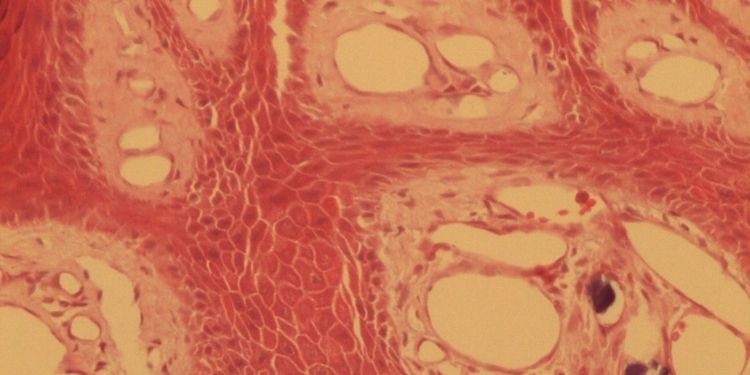

University of Obafemi University, Department of Oral and Maxillofacial Surgery and Oral Pathology, Ile-Ife.